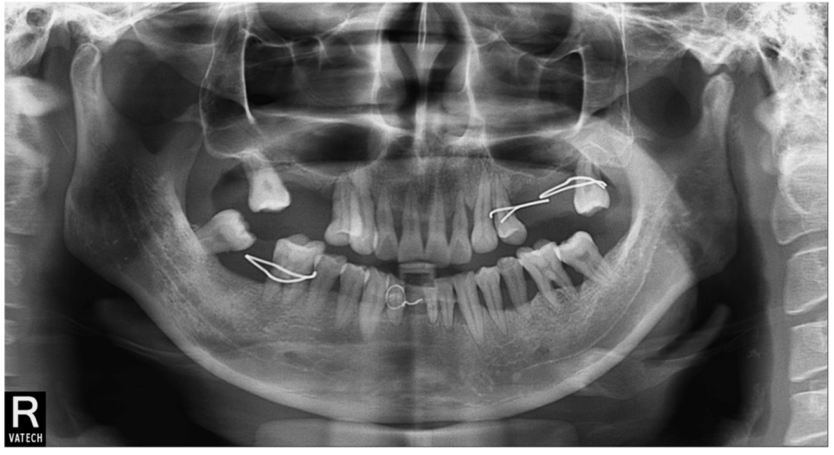

患者,女性,58岁,B7缺失,B6Ⅲ°松动。数码全景片示B6根折,根尖周阴影明显,骨质缺损明显(图17)。

图17 数码全景片(局部)显示B6牙槽骨吸收明显

因为B6根尖和牙周炎症较重,拔牙后没有即刻行拔牙位点保护术。拔牙2个月后,外提升术前CBCT示骨质缺损明显,剩余骨量不足以进行种植体植入(图18)。

图18 同一患者拔牙后2个月CBCT,骨量明显不足A.矢状位;B冠状位;C水平位